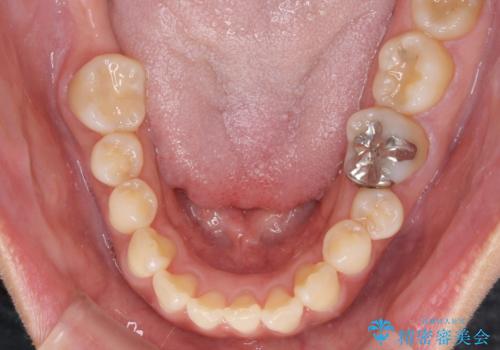

- 上下前歯の叢生を気にして来院された患者様です。

費用を抑え、期間もあまりかけずに治療をしたいとのことで、インビザライン・ライトを用いて矯正治療を行うこととしました。

インビザライン・ライトは、製作できるアライナーの枚数に制限があるため、移動可能な量に限りがあります。

一方で、半年から1年程度で治療を終えることができるため、軽度の歯列不正の患者様には大変お勧めです。